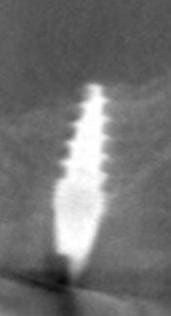

oui effectivement c est preferable des implants pas agressifs, sur la photo 7 on se rends plus compte que la pointe est plate...

effectivement c'est bien ca mais ce n'est pas quelque chose d'uniquement possible avec ces implants i, ca doit etre possible également avec d'autres marques (comme l'a précisé cingullum) il est important que le bout ne soit pas trop agressif et si on veut passer en flapless condenser avec un extenseur pas trop agressif non plus.

Le plus important dans un implant sont les 4 premiers millimètres crestales ( c'est pourquoi de nombreuses industries, NB, astra,Bio horizon... ont chosit de faire des implants avec des micro fissures crestales pour augmenter la surface sur ces premiers millimètres et garantir une meilleure stabilité 1aire et 2aire).La partie dans l'os spongieux est moins décisive. Dans un contexte comme celui ci le platform switching est un facteur à ne pas négliger.